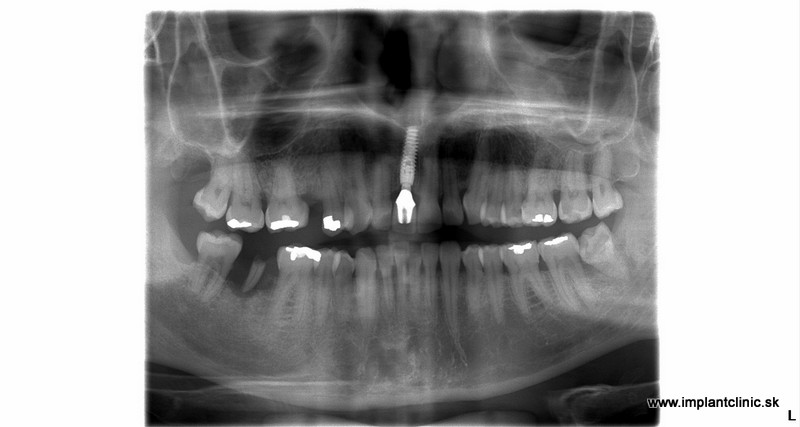

Prípadová Štúdia: Peter, 54 rokov, Bratislava

“Prišiel som o prednú dvojku po úraze. Bežný zubár mi navrhol mostík, ale to by znamenalo obrúsiť dva zdravé zuby. To som nechcel.”

Riešenie: Jeden implantát s keramickou korunkou

Výsledok: Po 6 mesiacoch má Peter zub, ktorý nerozoznáte od vlastných. Žiadne brúsenie. Žiadne kompromisy.

Cena: €1 350 (implantát + nadstavba + korunka)